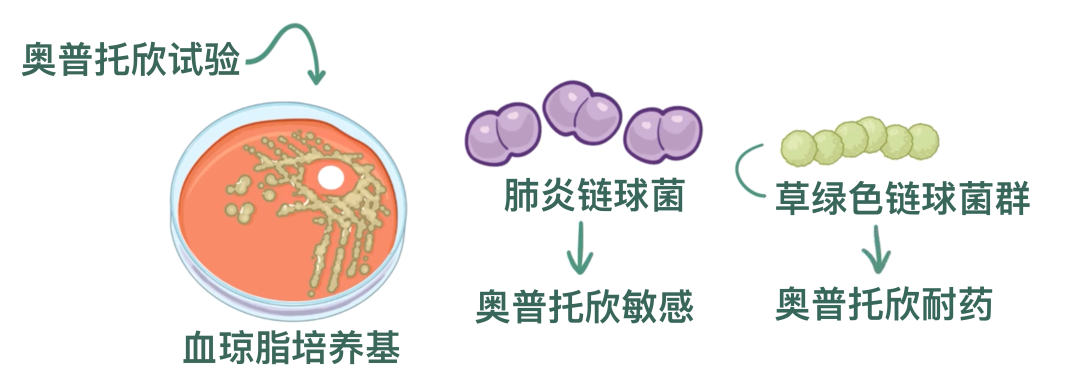

在一种叫做血琼脂的培养基上培养时,肺炎链球菌菌落会引起α溶血,也叫做绿色溶血。这是因为它们会产生过氧化氢,部分氧化了血琼脂中原本呈红色的血红蛋白,使之转变为绿色的高铁血红蛋白。

其他链球菌种类,比如草绿色链球菌(Streptococcus viridans),也同样表现为α溶血。

因此,为了区分肺炎链球菌,需要进行一种叫做optochin试验(奥普托欣实验)的检测,就是在培养物中滴加几滴乙基氢异烟酸。

肺炎链球菌对奥普托欣敏感,也就是说在加入奥普托欣后细菌会死亡,而草绿色链球菌对奥普托欣耐受,能够继续存活。